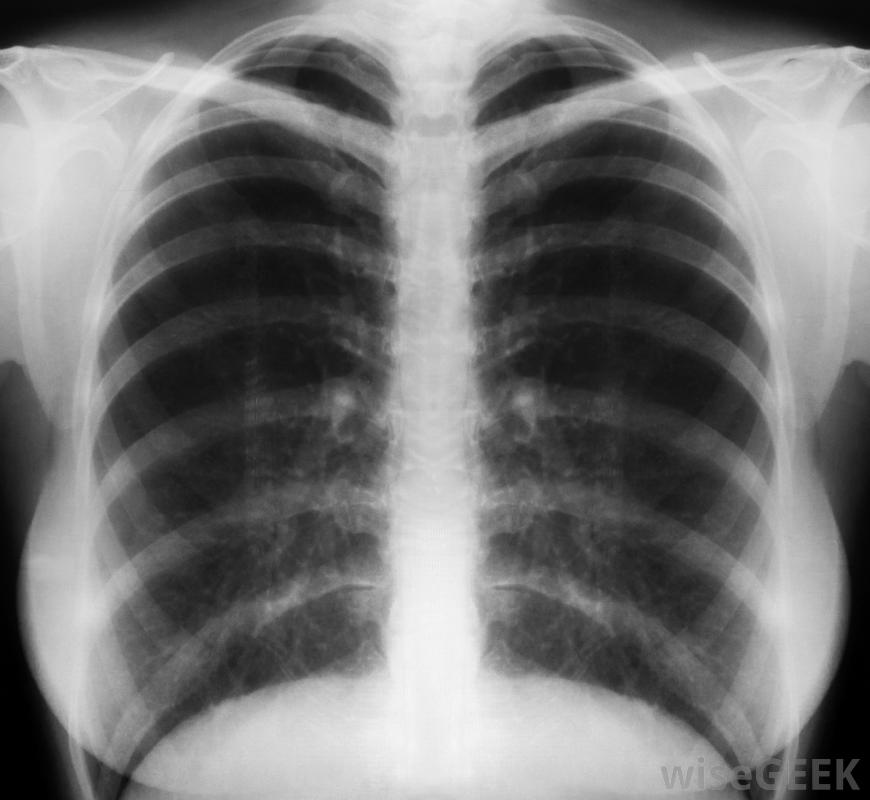

胸部x光片有助于结核病的诊断。

皮肤测试结果出来后,第一次检查通常是胸部X光片。X光片可以确定肺部是否有浸润或病变,这可能表明肺结核是活动性肺结核。通常还需要检查症状清单,以确定是否有结核病的症状,如体重减轻、咳血、发烧,如果胸部X光检查正常,没有任何症状,通常不需要进一步检查

当胸部X光片显示有肺结核的迹象或出现症状时,一个人可能患有活动性肺结核。此时,需要分析痰液样本以确认细菌的存在。患者还需要远离与其他人的密切接触,以防止疾病传播。如果存在活动性肺结核,则应使用抗生素药物治疗。